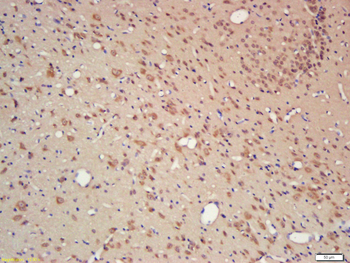

Anti-Cyclophilin A/PPIA Antibody [orb19174]

FC, ICC, IF, IHC, IHC-Fr, WB

Human, Mouse, Rat

Rabbit

Polyclonal

Unconjugated

10 μg, 100 μgCYPA Rabbit Polyclonal Antibody [orb100498]

FC, IF, IHC-Fr, IHC-P, WB

Bovine, Canine, Porcine, Rabbit

Human, Mouse, Rat

Rabbit

Polyclonal

Unconjugated